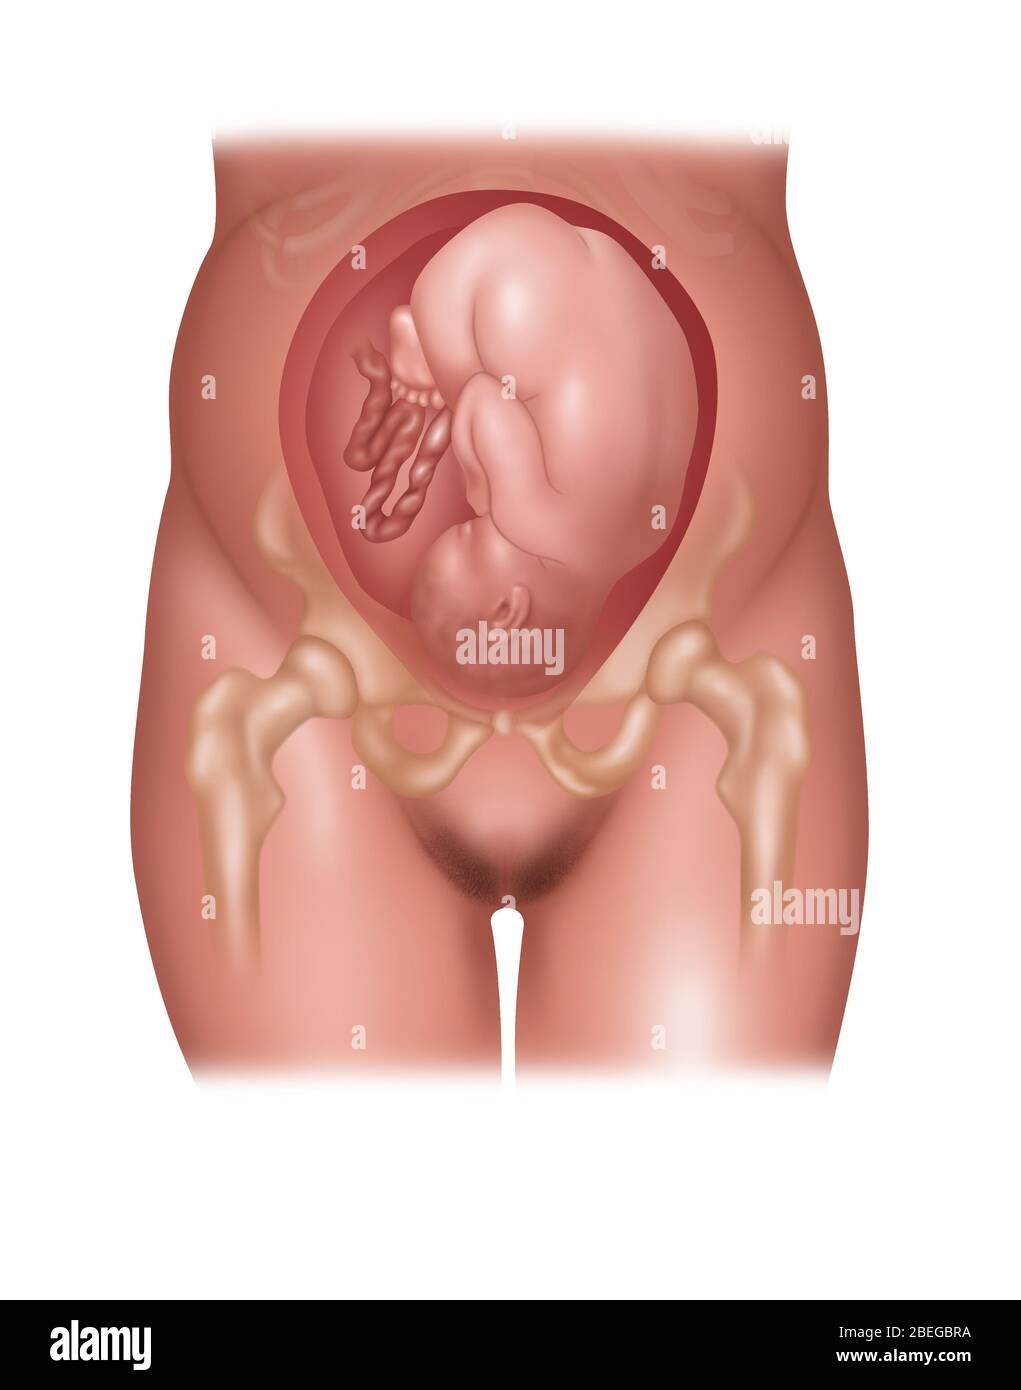

Childbirth, stage 1: the baby is engaged in the pelvis. Stock Photohttps://www.alamy.com/image-license-details/?v=1https://www.alamy.com/childbirth-stage-1-the-baby-is-engaged-in-the-pelvis-image476926081.html

Childbirth, stage 1: the baby is engaged in the pelvis. Stock Photohttps://www.alamy.com/image-license-details/?v=1https://www.alamy.com/childbirth-stage-1-the-baby-is-engaged-in-the-pelvis-image476926081.htmlRF2JKWT29–Childbirth, stage 1: the baby is engaged in the pelvis.